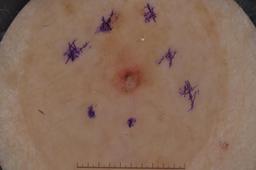

{

"age_approx": 40,

"anatom_site_general": "lower extremity",

"concomitant_biopsy": true,

"dermoscopic_type": "contact non-polarized",

"diagnosis_1": "Benign",

"diagnosis_2": "Benign melanocytic proliferations",

"diagnosis_3": "Nevus",

"diagnosis_confirm_type": "histopathology",

"image_type": "dermoscopic",

"lesion_id": "IL_0404349",

"melanocytic": true,

"sex": "female"

}